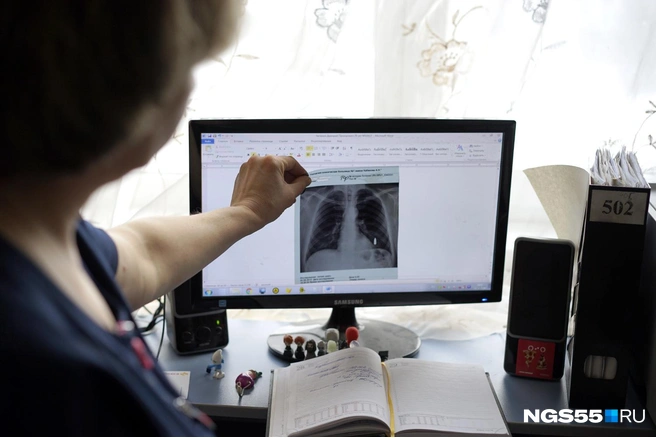

Глядя на экран

Отделение торакальной хирургии в омской горбольнице имени Кабанова открыли в 1983 году. Сегодня в штате трудятся шесть врачей и 19 медсестёр. Больных значительно больше — уже 35 лет сюда со всего города круглосуточно свозят больных с ранениями груди и другими неприятностями с дыхательной системой.

— Бытовые и криминальные травмы, попытки суицидов... Делаем операции на легких, трахее, пищеводе, средостении. В том числе высокотехнологичные видеоторакоскопические, — рассказывает Юлия Никитина, исполняющая обязанности завотделением.

Если простым языком — через прокол в груди хирург вводит эндоскопические инструменты в полость тела и проводит операцию. Через другой прокол вводится специальная видеокамера с фокусировкой и вспышкой — темно внутри! — и транслирует изображение на монитор. Хирург, соответственно, делает свою работу, глядя на экран. Это называется видеоскопической резекционной операцией.